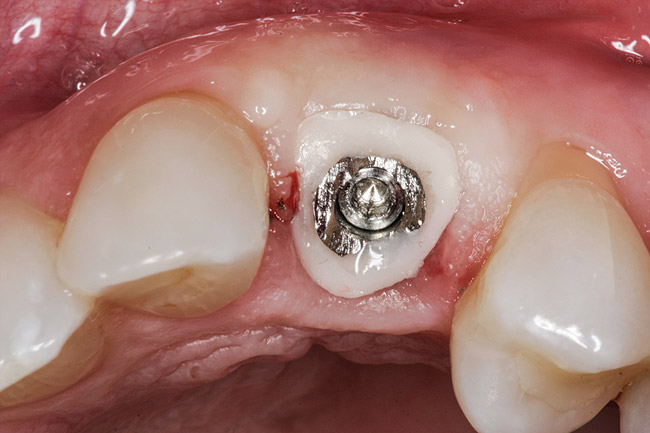

Fig 9. Custom healing abutment in place, with blanching present upon insertion.

Figure 9

Figure 9 shows a custom healing abutment in place; notice the blanching present upon insertion. This reflects the amount of tissue slumping that existed in the short time it took to fabricate the custom healing abutment. An advantage of this type of healing abutment is that it allows a removable provisional restoration to be made for the patient. The main shortcoming of the removable type of provisional, however, is that the soft-tissue support gained from the pontic is only present while the provisional is worn, making this approach highly dependent on patient compliance. If the patient leaves the provisional out for extended periods of time or loses it, the soft tissue will no longer be held in the proper relationship. By having the custom healing abutment underneath the removable prosthesis, the soft tissues are always being held in the proper position. It can also be used under bonded provisionals as well.